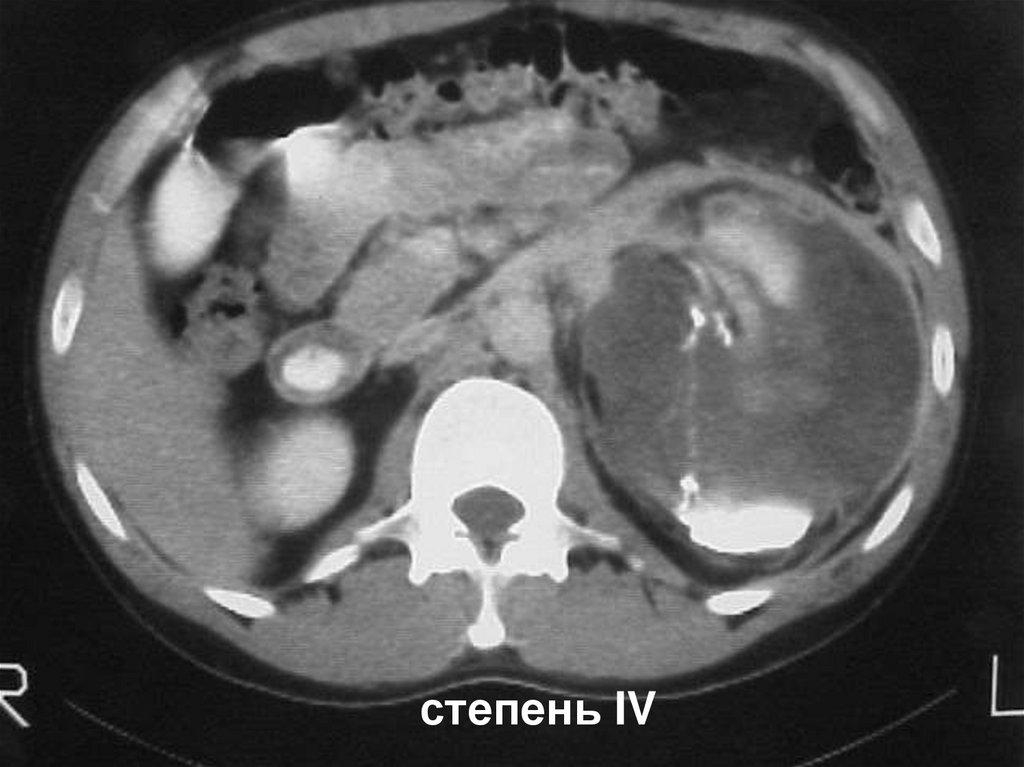

18.

степень IV

19.

Размозжение почки или отрыв от почечной ножки

20.

степень V